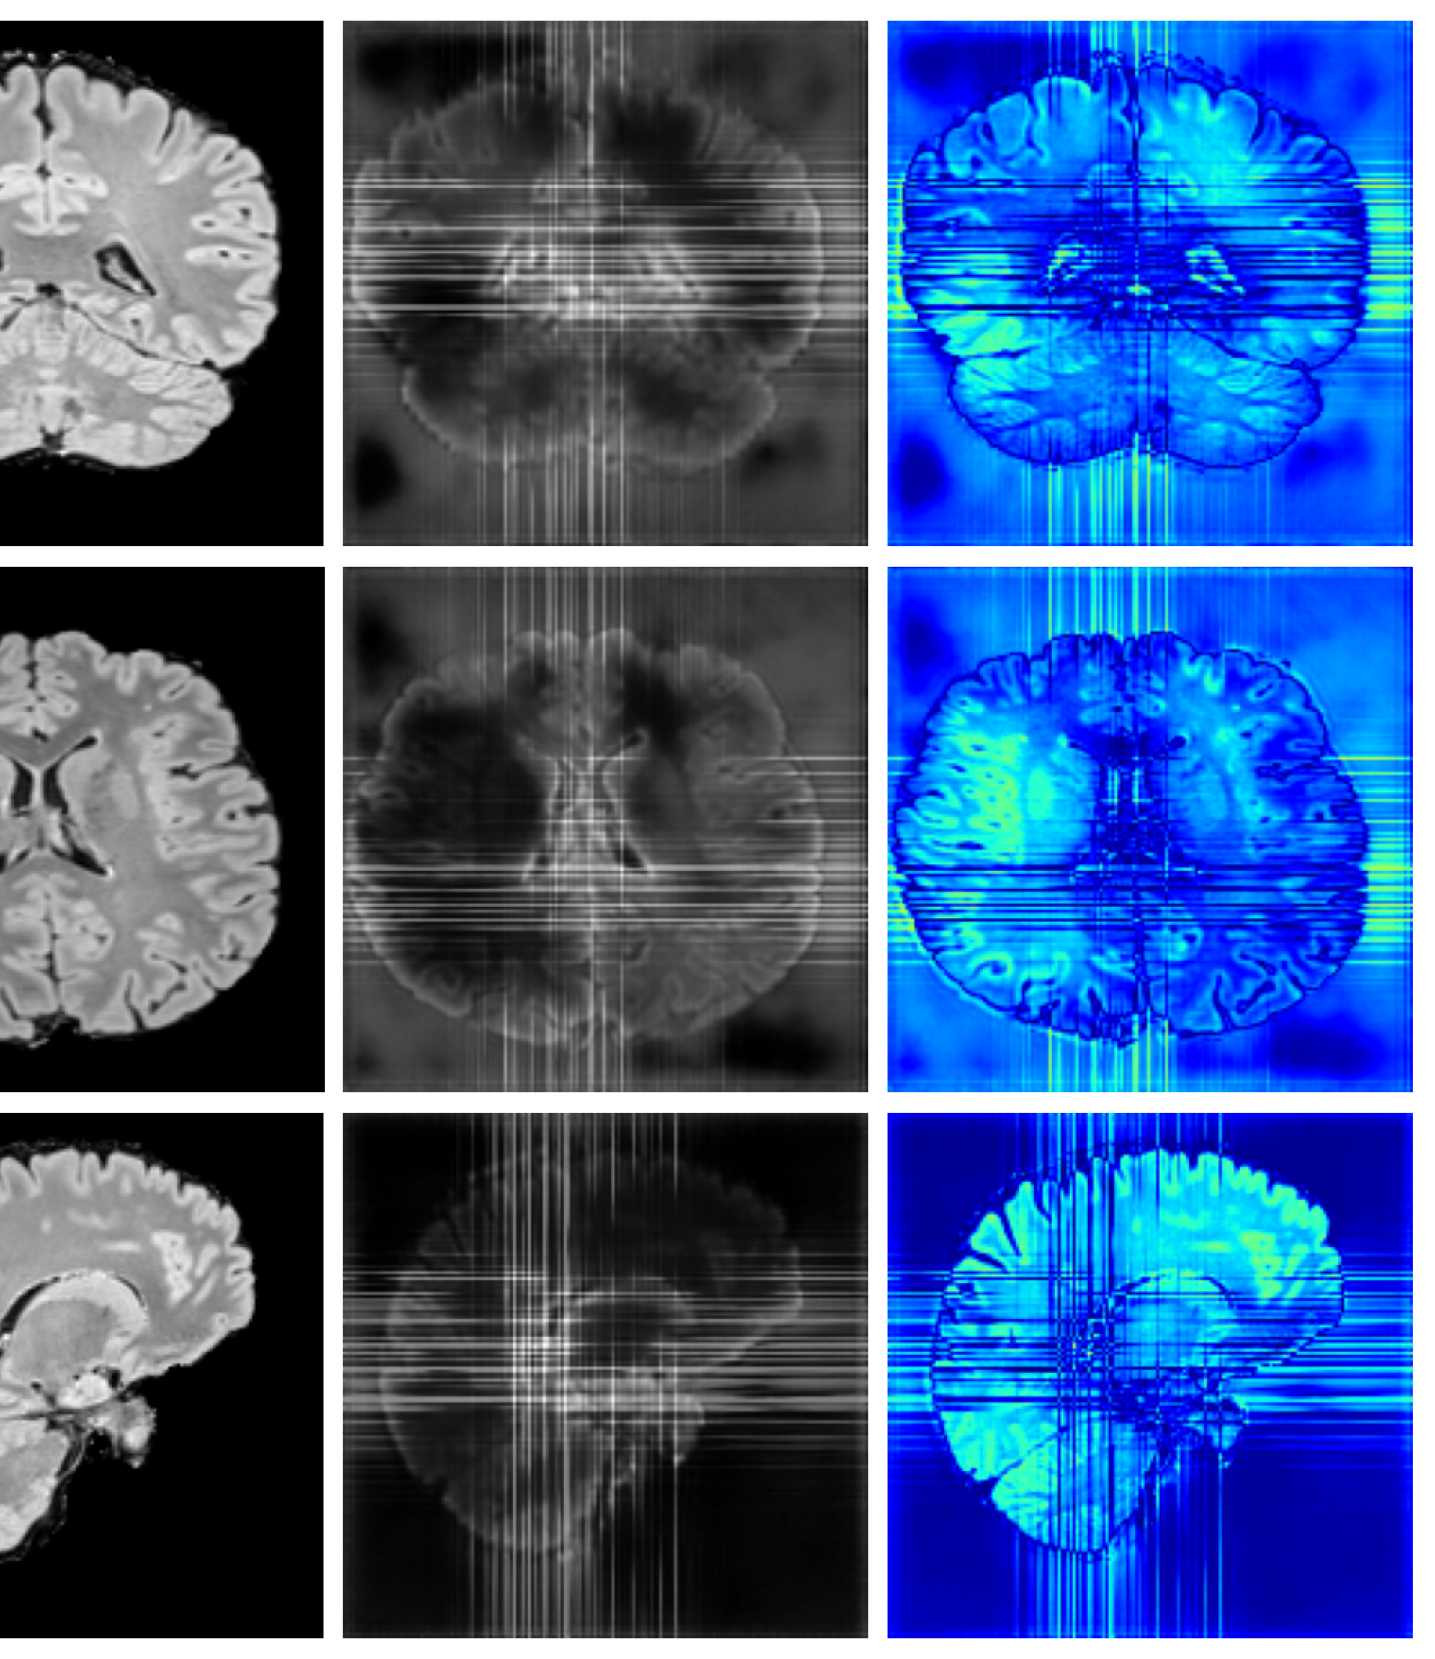

4.4 Image refinement results

The image refinement results (see Appendix A.10 for more examples) in Figure 4 highlight our framework’s ability to enhance outputs from existing methods. While SynthSR can inpaint disease regions, the resulting tissue often appears unrealistic. Our method further refines these areas, producing anatomically plausible reconstructions with more realistic surface structures.

A.10 Additional qualitative refinement results

Additional qualitative refinement results for subjects from the ATLAS dataset are given in Figure 14